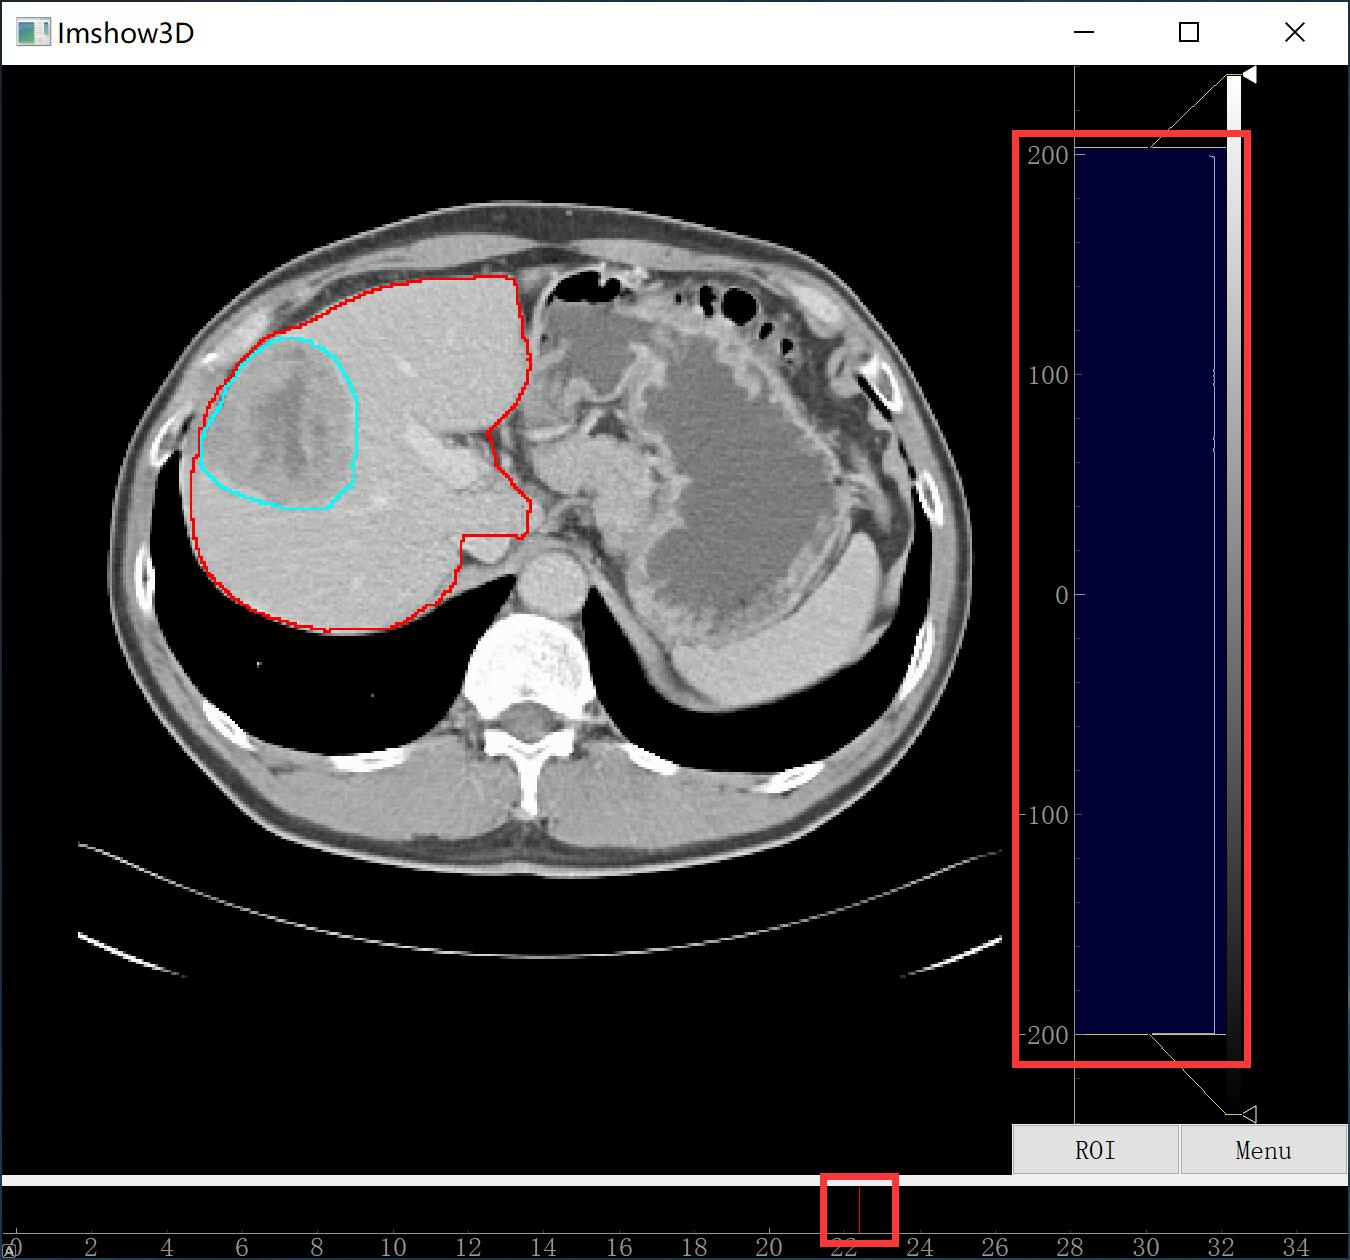

2. Python 代码查看 .nii 文件

相关的代码见我的 github:地址

我给出了两个代码,一个是可以同时显示器官、器官分割结果、肿瘤分割结果的,另一个是只显示器官的。当然,大家可以在第一个的基础上做改动。与 ITK-SNAP 不同,在显示的时候只显示分割结果的边界,这样更有利于观察分割的是否合理。并且还可以通过调节上图中右边红框中的滑块来调节图像灰度值的范围,通过调节上图中下方红框中滑块来查看不同横截面的图像。